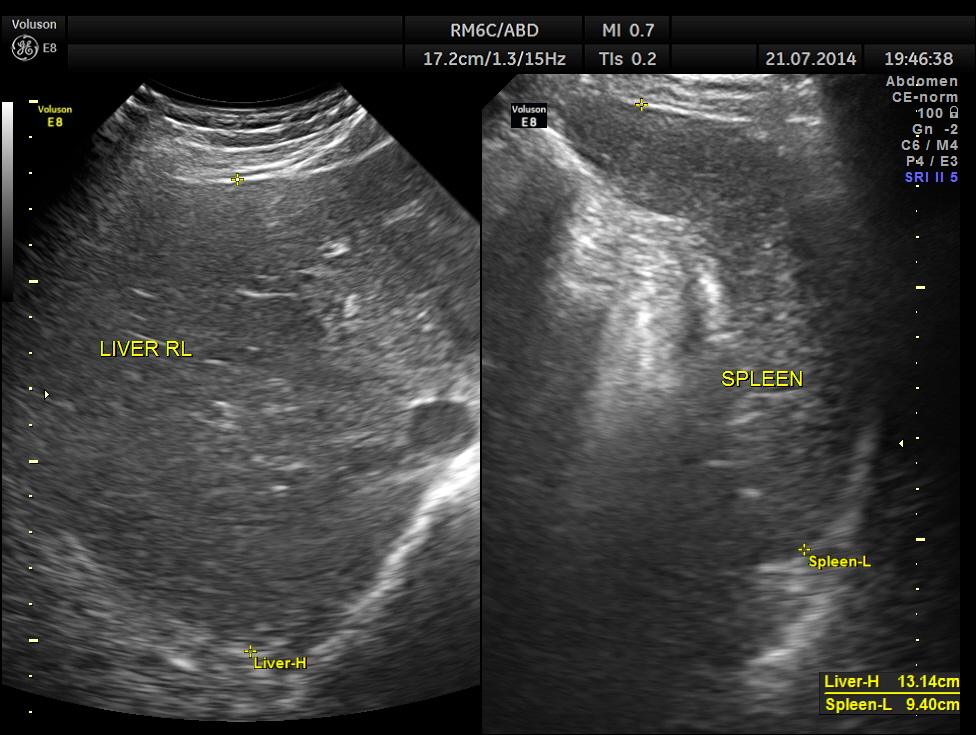

This was a 42-year-old gentleman , a known case of Insulin dependant Diabetes Mellitus. He was being evaluated by his physician for loss of weight and abdominal pain of a few months duration.

His abdominal ultrasound pictures are given below.